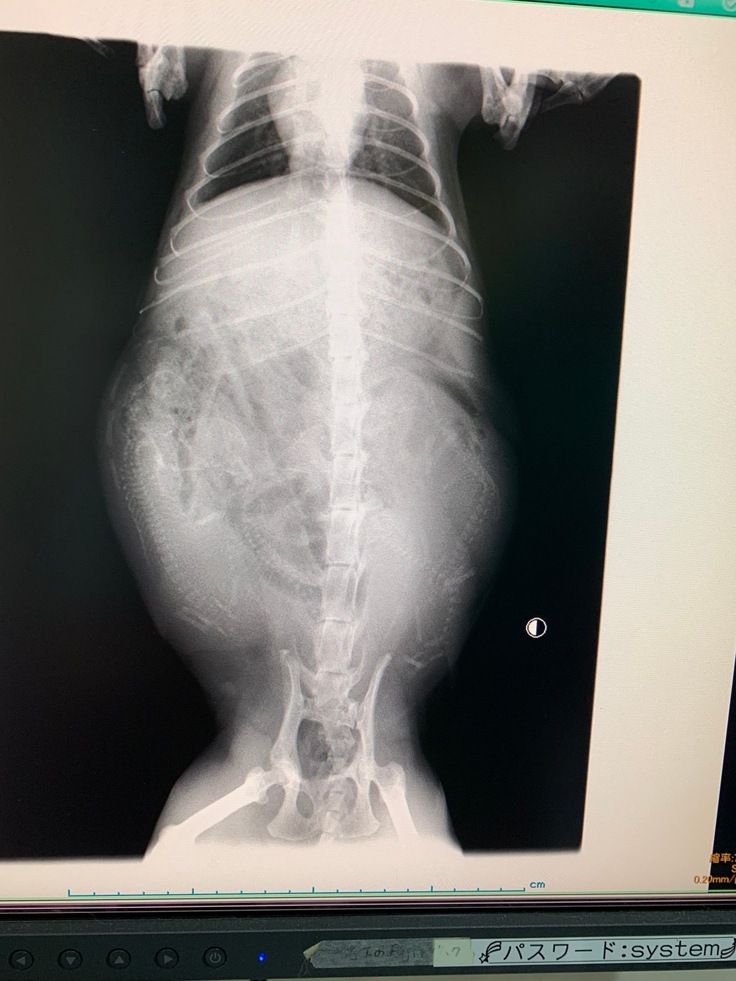

さる2年前の夏。幼猫ハイジのまさかの妊娠が発覚しました。

ハイジのお腹の中に、4体の胎児が確認されました。

夏真っ盛り。重くなるお腹に耐えるハイジ。